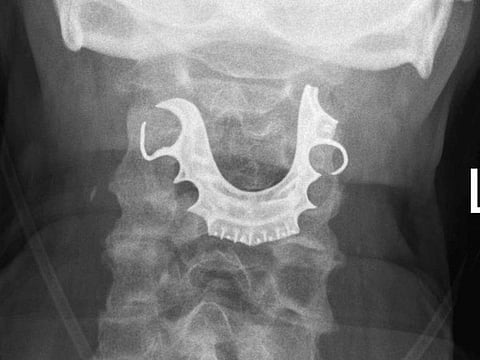

Tests, conducted for the man at the hospital’s emergency department, showed that the denture clung to the upper part of the oesophagus with the metal tip of the denture stuck in the organ’s wall.

An emergency endoscopy was performed on him. The procedure successfully led to the removal of the denture.